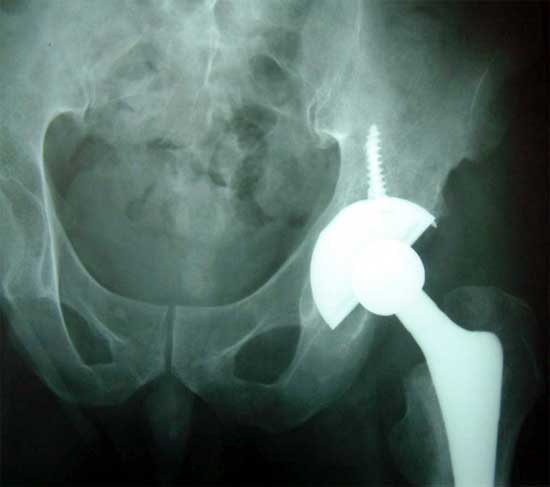

髋臼嗜酸性肉芽肿,臼顶骨破坏 刮除病灶,复合BMP的脱钙异体骨基质修复骨缺损,全髋关节置换术后1年